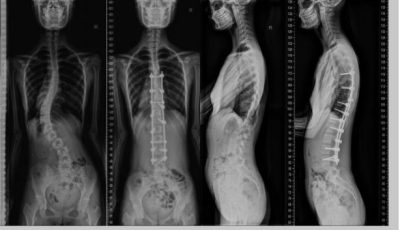

全嵴柱X线摄影:便捷、低剂量的嵴柱健康“侦察兵”

当医生怀疑嵴柱侧弯、骨折或退行性疾病时,全嵴柱X线摄影常作为首选检查手段。这项看似简单的影像学检查,凭借其快速、经济、低辐射的特点...